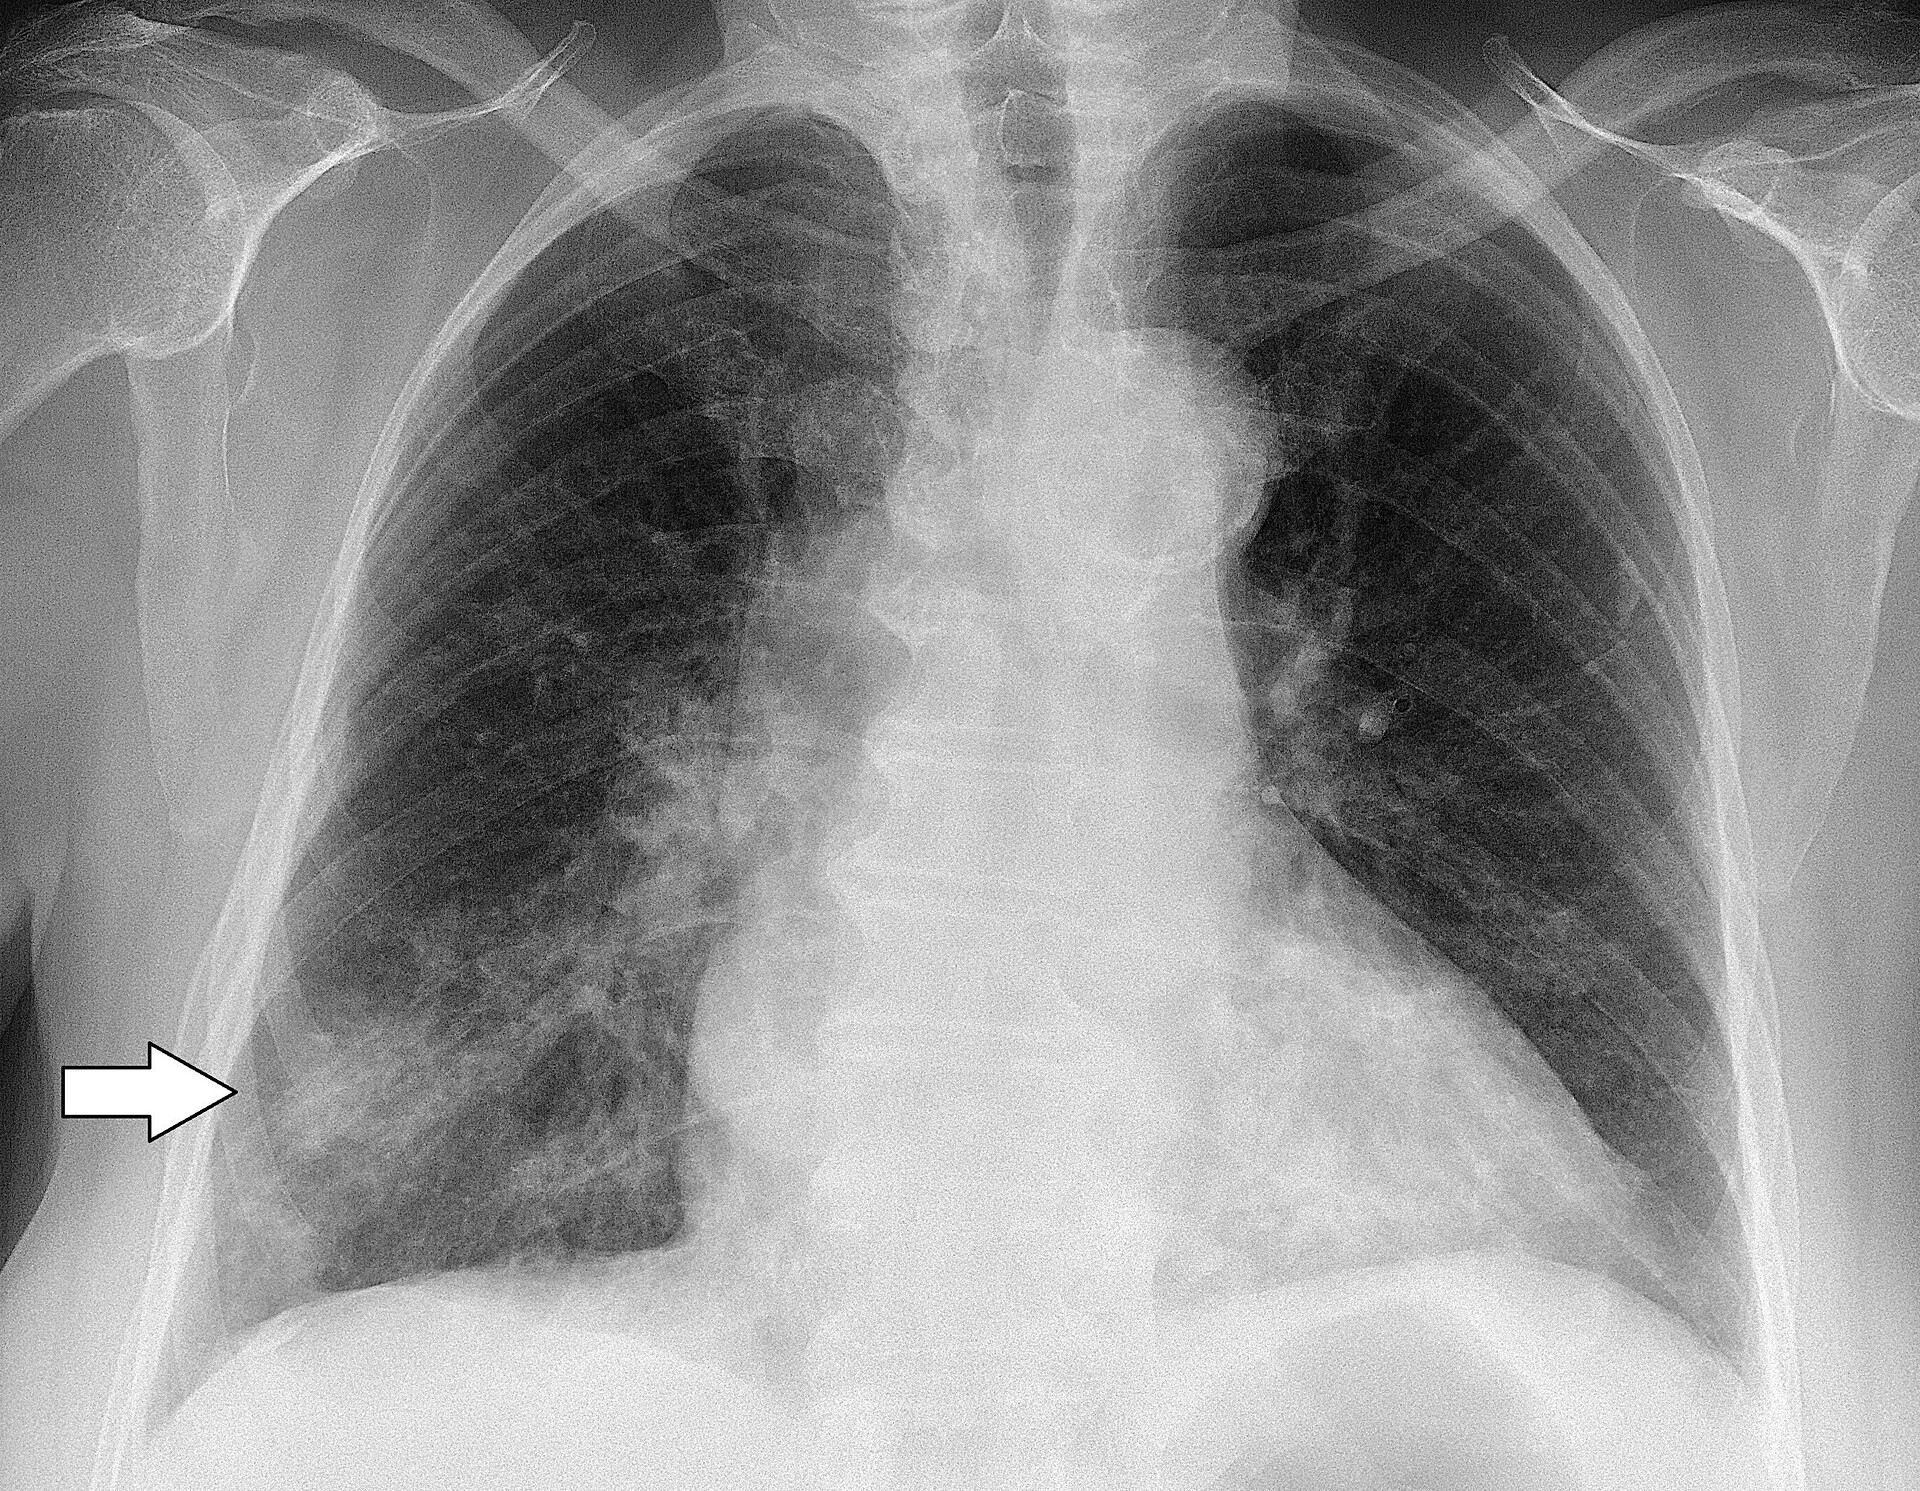

Clinical features of a respiratory tract infection may include initial symptoms of an upper respiratory tract infection mimicking a viral infection, usually associated with low-grade fevers. This may progress to the lower respiratory tract within a few days, with features often resembling those of wheezy bronchitis. Sputum may be difficult to expectorate and is often grey or creamy in color. The cough may persist for weeks without appropriate treatment. Many cases are diagnosed after presenting chest infections that do not respond to penicillins or first-generation cephalosporins. A chest X-ray can identify alveolar consolidation.